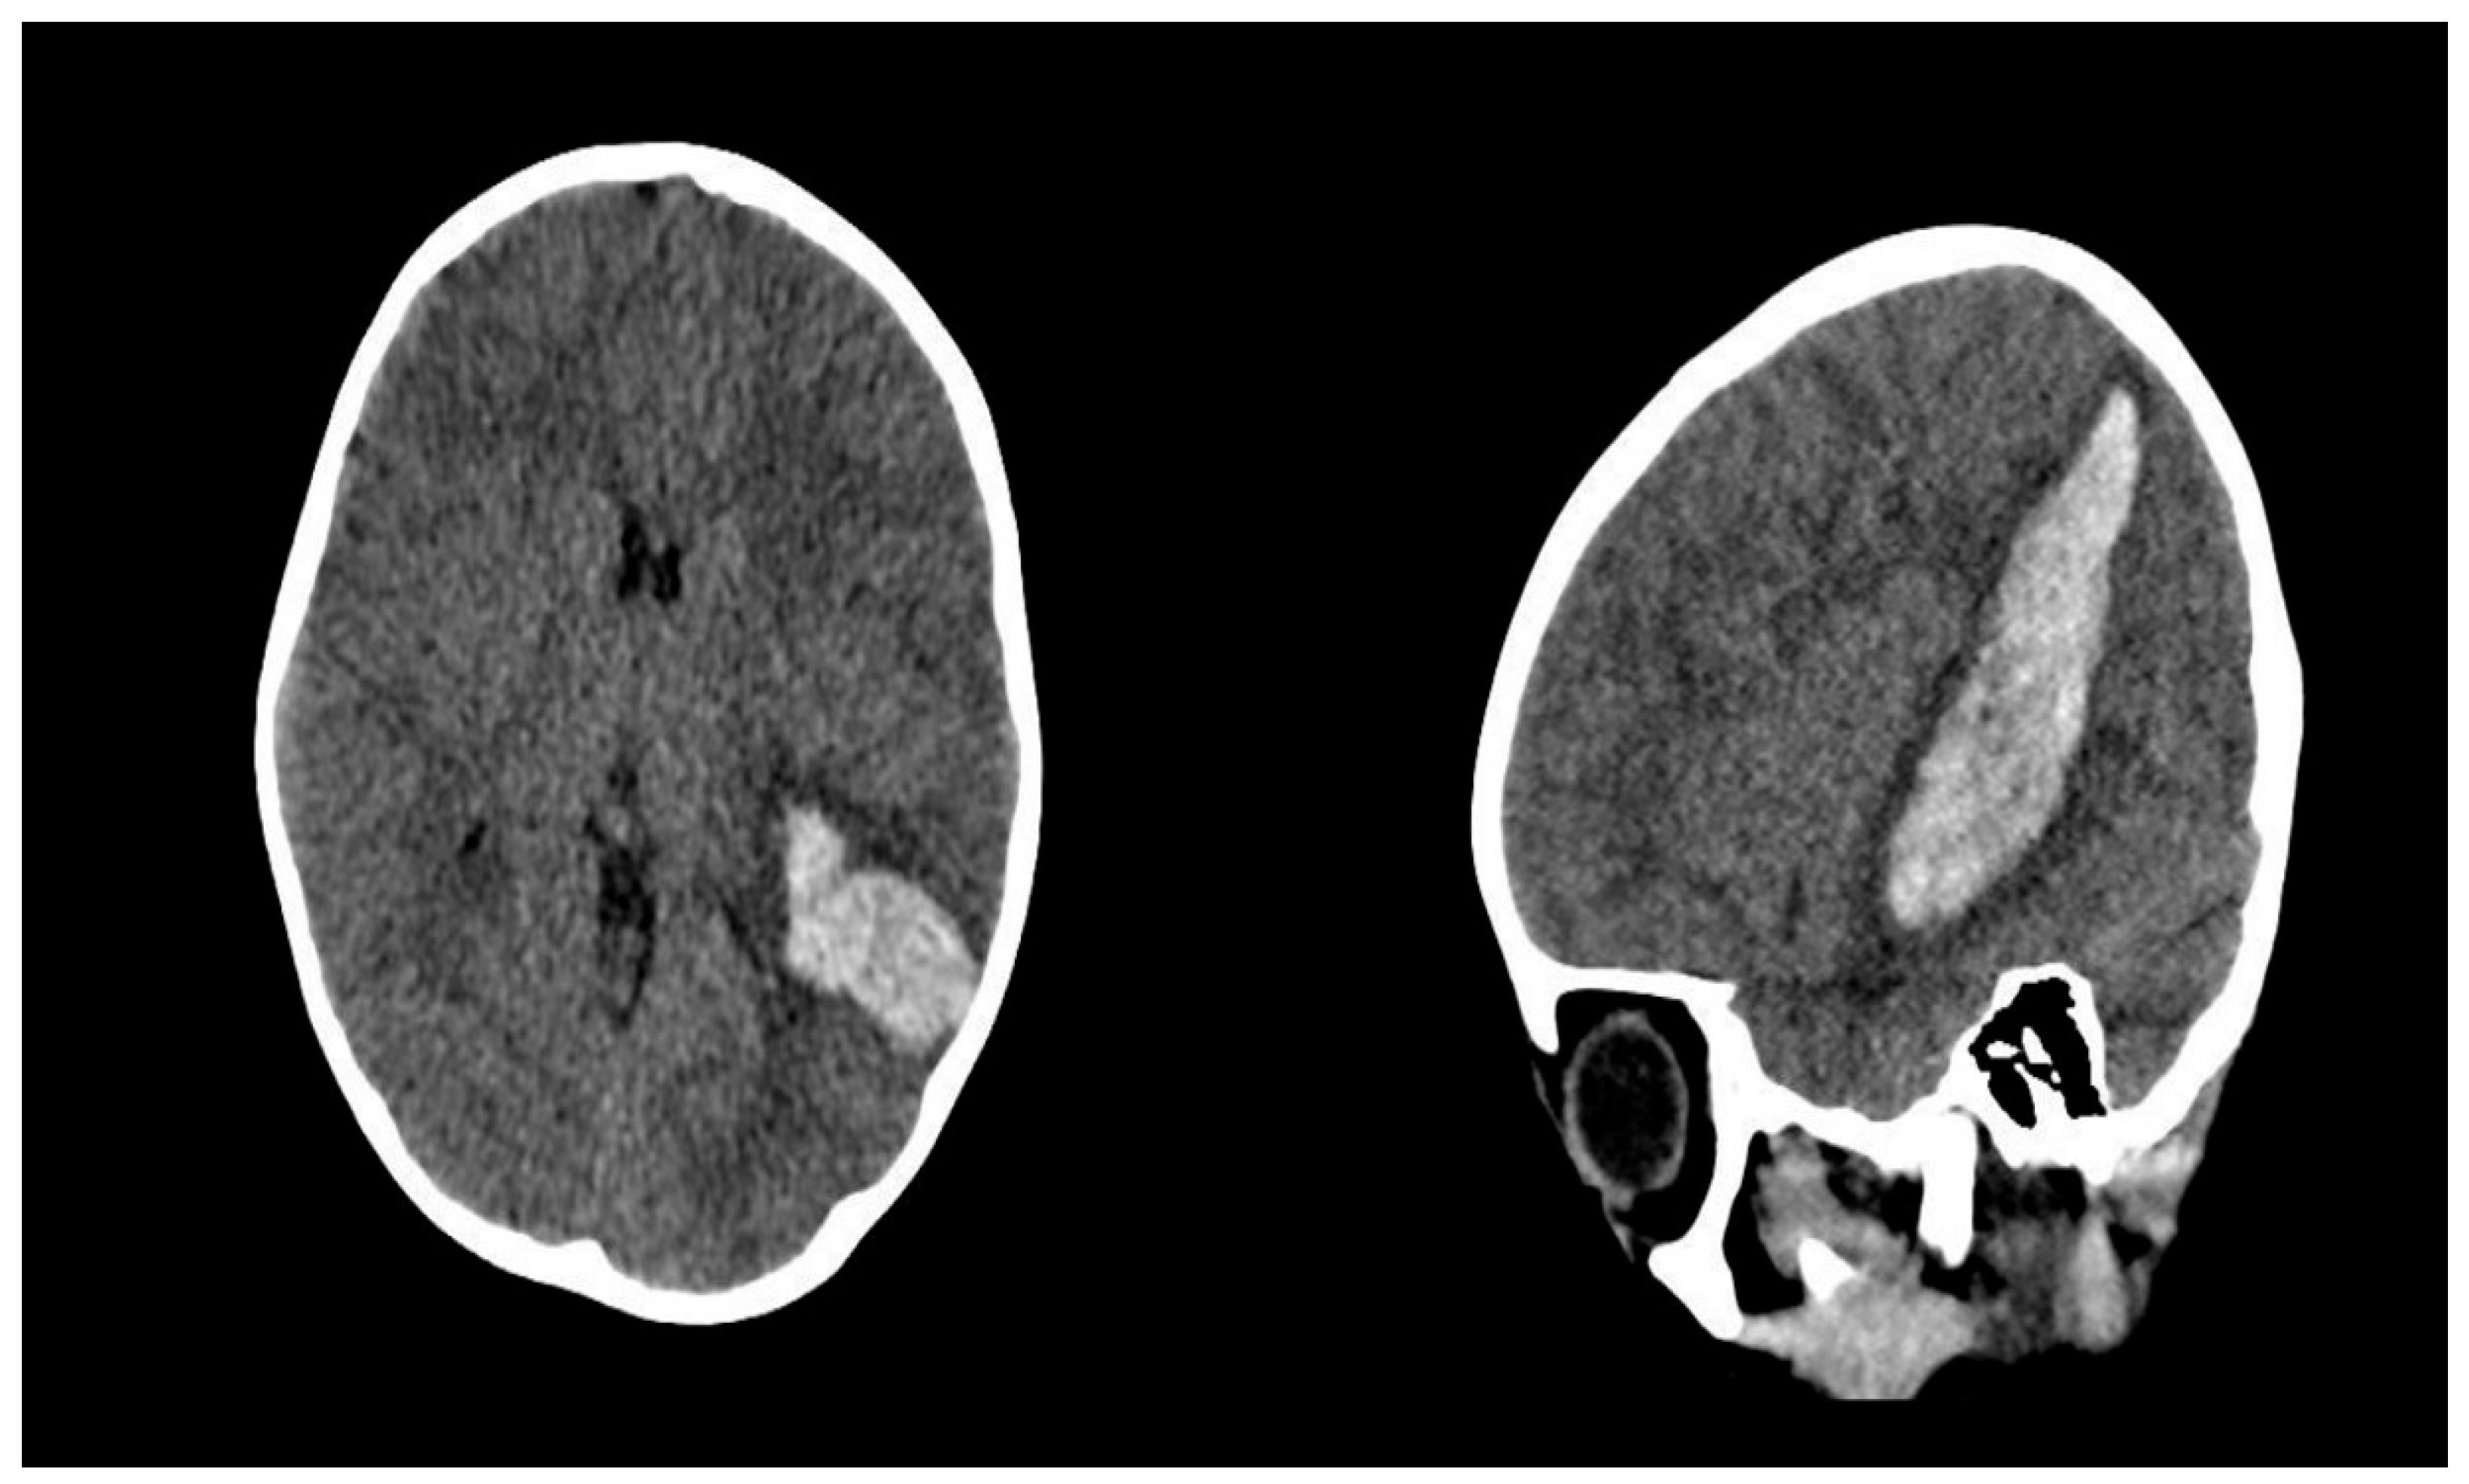

After two years, the patient was re-admitted to the emergency department with complaints of headache and seizures. A brain CT scan revealed a recurrent intracerebral hematoma in the left posterior temporal region, corresponding to the site of the previous hemorrhage (Figure 4).

Figure 4. Cranial CT scans obtained following recurrent intracerebral hemorrhage.